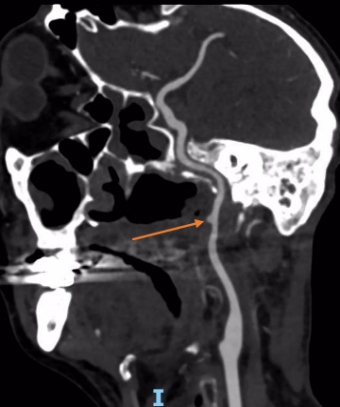

入院后,治疗团队为其完善血管头颈部CTA检查,发现肿瘤包绕颈内动脉,左侧颈内动脉肿瘤包绕处可见假性动脉瘤,基底动脉环显示左侧后交通动脉粗大。

箭头所指为假性动脉瘤